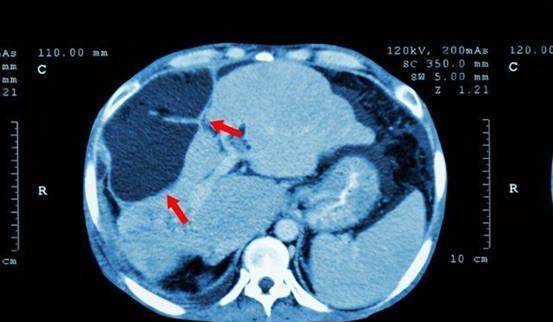

医生通过化验单,发现刘女士的转氨酶与甲胎蛋白都高于正常数值,已经高达468ng/ml,于是又为刘女士做了肝脏CT。

医生通过CT影像,发现刘女士的肝脏上已经出现了5cm大小的肿块,进一步检查确定为肝病。